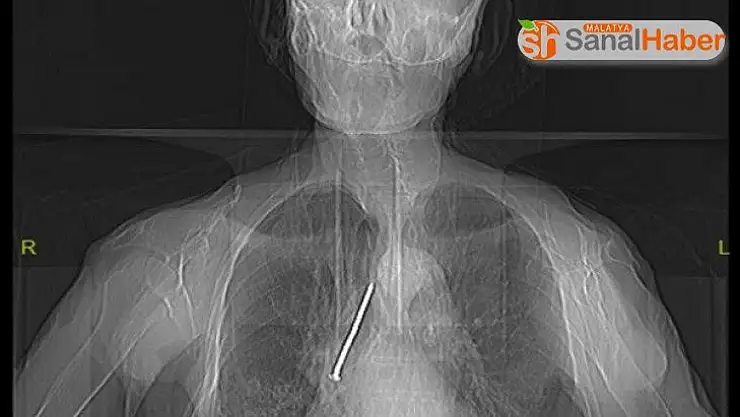

Soluk borusuna kaçan 10 santimlik çivi çıkarıldı

Elazığ’da, hastaneye başvuran 91 yaşındaki Keko Ateş’in nefes borusuna kaçan 10 santimetrelik inşaat çivisi, yapılan operasyonla başarılı bir şekilde çıkarıldı.

Elazığ’da, boynundan nefes borusuna açılan açıklık aracılığıyla solunumunu sağlayan Keko Ateş (91), öksürük ve nefes darlığı şikayetiyle Fethi Sekin Şehir Hastanesine başvurdu. Burada yapılan tetkik ve muayeneler sonucu yaşlı adamın nefes alıp verdiği boşluğu temizlemek için kullandığı 10 santimetrelik çivinin soluk borusuna kaçtığı belirlendi. Hayati tehlike oluşturan çivi, Göğüs Cerrahi Uzmanı Dr. Öğretim Üyesi Murat Kılıç tarafından “Rijit Bronskoskopi” işlemi ile çıkarıldı. Yaşlı adam çivinin çıkarılmasından kısa süre sonra hasta taburcu edildi.

Hızlı bir şekilde müdahale edilmediği takdirde hayatı tehlikeye atabilen bir durumla karşı karşıya kaldıklarını belirten Dr. Kılıç, "Larenks kanseri nedeniyle 24 yıl önce boynundan nefes borusuna açılan açıklık aracılığıyla nefes alıp verebilen hasta, nefes borusundaki bu açıklığı temizlemek amacıyla kullandığı 10 santimlik çiviyi soluk borusuna kaçırmış. Bu nedenle gelişen öksürük ve nefes darlığı şikayeti ile önce başka bir sağlık merkezine başvurmuş, ardından Fethi Sekin Şehir Hastanemiz Göğüs Cerrahisi Kliniğine yönlendirilmiş. Biz de hastanede 91 yaşındaki hastamıza çektiğimiz tomografide soluk borusu içerisinde, sağ akciğer içerisine doğru kaçmış olan çiviyi tespit ettik” dedi.

Bunun üzerine hastayı acil olarak ameliyata aldıklarını aktaran Kılıç, “Uyguladığımız Rijit Bronskoskopi işlemi ile nefes borusundaki 10 santimetrelik çiviyi başarılı bir şekilde çıkardık. Hastamızı ameliyat sonrası bir süre serviste takip ettikten sonra gün içerisinde şifa ile taburcu ettik. Nadir de olsa bu tarz durumlarla karşılaşıyoruz. Bu tür durumlarda hızlı müdahale etmek oldukça önemli. Trakeostomili hastaların bu şekilde yabancı cisimlerle soluk borusuna müdahale etmemeleri gerekiyor” diye konuştu.